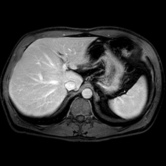

The category discovery clusters employing our LDPO method are found to be more visually coherent and cluster-wise balanced in comparison to the results in [44] where clusters are formed only from text information ( radiology reports). Fig. 4 Left shows the image numbers for each cluster from the AlexNet-FC7-Topic setting. The numbers are uniformly distributed with a mean of 778 and standard deviation of 52. Fig. 4 Right illustrates the relation of clustering results derived from image cues or text reports [44]. Note that there is no instance-balance-per-cluster constraints in the LDPO clustering. The clusters in [44] are highly uneven: 3 clusters inhabit the majority of images. Fig. 5 shows sample images and top-10 associated key words from 4 randomly selected clusters (more results in the supplementary material). The LDPO clusters are found to be semantically or clinically related to the corresponding key words, containing the information of (likely appeared) anatomies, pathologies (e.g., adenopathy, mass), their attributes (e.g., bulky, frontal) and imaging protocols or properties.

Next, from the best performed LDPO models in Table 2, AlexNet-FC7-Topic has Top-1 classification accuracy of 0.8109 and Top-5 accuracy 0.9412 with 270 formed image categories; AlexNet-FC7-ImageNet achieves accuracies of 0.8099 and 0.9547, respectively, from 275 discovered classes. In contrast, [44] reports Top-1 accuracies of 0.6072, 0.6582 and Top-5 as 0.9294, 0.9460 on 80 text only computed classes using AlexNet [27] or VGGNet-19 [47], respectively. Markedly better accuracies (especially on Top-1) on classifying higher numbers of classes (being generally more difficult) highlight advantageous quality of the LDPO discovered image clusters or labels. This means that the LDPO results have rendered significantly better performance on automatic image labeling than the most related previous work [44], under the same radiology database. After the subjective evaluation by two board-certified radiologists, AlexNet-FC7-Topic of 270 categories and AlexNet-FC7-ImageNet of 275 classes are preferred, out of total six model-encoding setups. Interestingly, both CNN models have no deep feature encoding built-in and preserve the gloss image layouts (capturing somewhat global visual scenes without unordered FV or VLAD encoding schemes [9, 8, 21].).

The final trained CNN classification models allow to compute the pairwise category similarities or affinity scores using the CNN classification confusion values between any pair of classes (Sec. 3.5). Affinity Propagation algorithm is called recursively to form a hierarchical category tree. The resulted category tree has (270, 64, 15, 4, 1) different class labels from bottom (leaf) to top (root). The random color coded category tree is shown in Fig. 6. The high majority of images in the clusters of this branch are verified as CT Chest scans by radiologists. Enabling to construct a semantic and meaningful hierarchy of classes offers another indicator to validate the proposed LDPO category discovery method and results. Refer to the supplementary material for more results. We will make our trained CNN models, computed deep image features and labels publicly available upon publication.